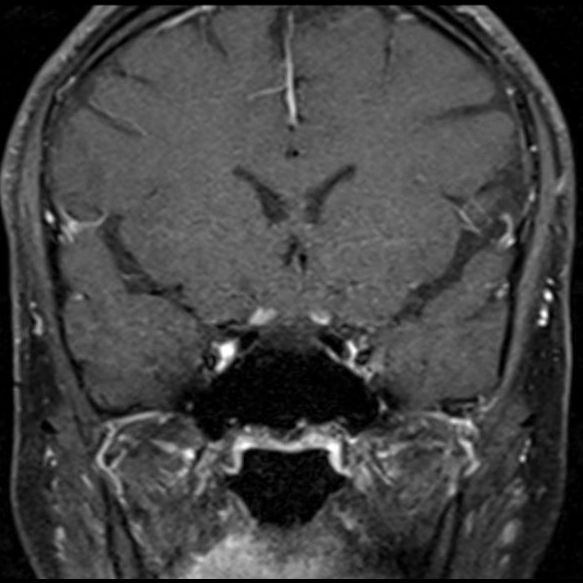

- (B) Orbita MRG’de aksiyel yağ baskılı T1A’da optik sinir prekiazmatik segmenti (oklar) gösterilmiş olup sırası ile aksiyel ve koronal post-kontrast yağ baskılı T1A görüntülerde bilateral optik sinir prekiazmatik segmentte kontrast tutulumu dikkati çekmektedir (oklar ve daire).

- Optik nörit varlığında özellikle optik kiazma ve posterior optik sinir tutulumu görülür ve bilateral olabilir.

- MS’de optik nörit radyolojik tutulumu daha fokal iken NMO spektrum bozukluğu ve MOGAD’de genellikle daha yaygındır. MOGAD, NMO’ya kıyasla daha anterior kısmı etkileme eğilimindedir.

- Kontrast madde enjeksiyonu sonrasında neredeyse tüm akut NMO lezyonları, yamalı, düzensiz veya periferik olarak kontrastlanma gösterir.